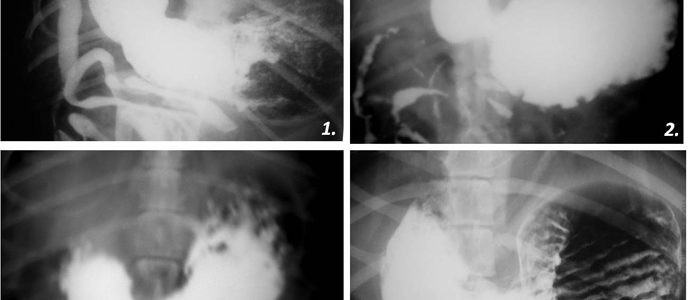

Рентгеноконтрастные Исследования Кишечника: Визуализация и Методики

Раздел: Иллюстрированный журнал